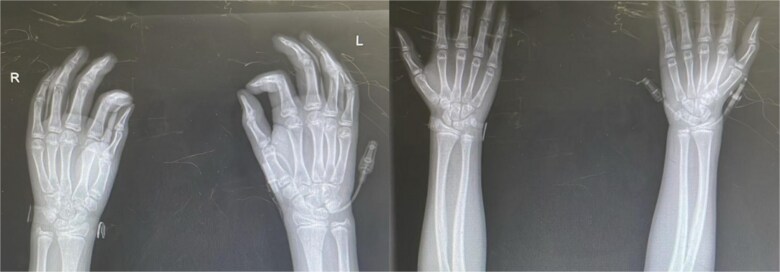

性早熟是一种罕见的情况,特别是在男孩中,其特点是第二性特征的早期发展。本病例报告介绍了一名来自危地马拉农村的5岁男性,他表现出性成熟加速的迹象,包括Tanner期IV生殖器、阴毛和面部毛发以及骨龄提前。经评估,诊断与慢性营养不良和社会心理压力等环境因素有关,这些因素可能导致下丘脑-垂体-性腺轴过早激活。在资源匮乏的环境中,贫困、获得医疗保健的机会有限和营养缺乏等因素会严重影响生长发育,导致性早熟等非典型症状。这一案例突出了在诊断和管理青春期时考虑环境因素和健康的社会决定因素的重要性,特别是在服务不足的人群中。

Precocious puberty is a rare condition, particularly in boys, characterized by the early development of secondary sexual characteristics. This case report presents a 5-year-old male from rural Guatemala who exhibited signs of accelerated sexual maturation, including Tanner stage IV genitalia, pubic and facial hair, and advanced bone age. After evaluation, the diagnosis was associated with environmental factors such as chronic malnutrition and psychosocial stress, which likely contributed to the premature activation of the hypothalamic-pituitary-gonadal axis. In low-resource settings, factors like poverty, limited access to healthcare, and nutritional deficiencies can significantly impact growth and development, leading to atypical presentations of conditions like precocious puberty. This case highlights the importance of considering environmental factors and social determinants of health when diagnosing and managing puberty, especially in underserved populations.